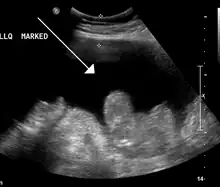

Ascites in a person with abdominal cancer as seen on ultrasound

Liver cirrhosis with ascites

Ultrasound investigation is often done before attempts to remove fluid from the abdomen. This may reveal the size and shape of the abdominal organs, and Doppler studies may show the direction of flow in the portal vein, as well as detecting Budd–Chiari syndrome (thrombosis of the hepatic vein) and portal vein thrombosis. The sonographer also can estimate the amount of ascitic fluid, and difficult-to-drain ascites may be drained under ultrasound guidance. An abdominal CT scan is more accurate than a sonogram to reveal abdominal organ structure and morphology.[12]